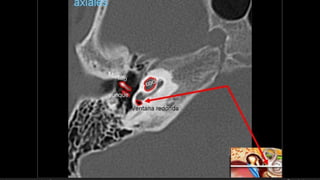

Evaluación Imagenologica

• #38 Izqu. AXIAL-- fxLongitudinal perdonan la capsula otica (laberinto oseo) Centro AXIAL fx trnasversa lascuales tperdonan el lab erinto oseo Dere: MIXTA – tmp perdona